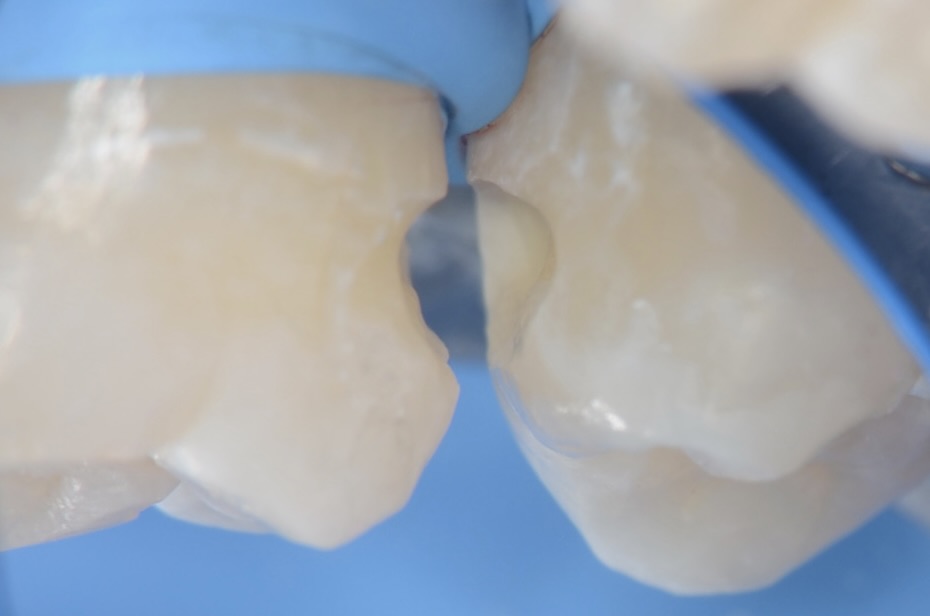

ダイレクトボンディング

フロワブルレジンの表面張力を利用して滑らかに充填します。 -

口蓋側面観

手間はかかりますがこれによって、隙間から治療することで、歯を削る量を減らします。 -